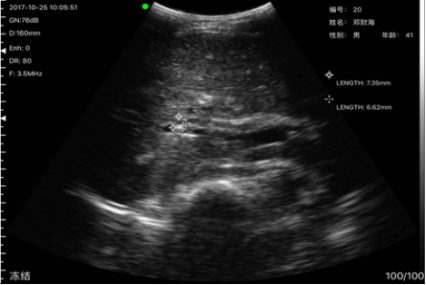

病例3姓名:杨x春,性别:男,年龄69岁,通过掌上B超设备检测发现其肝部有异物,到沙县医院复诊确诊为肝血管瘤。